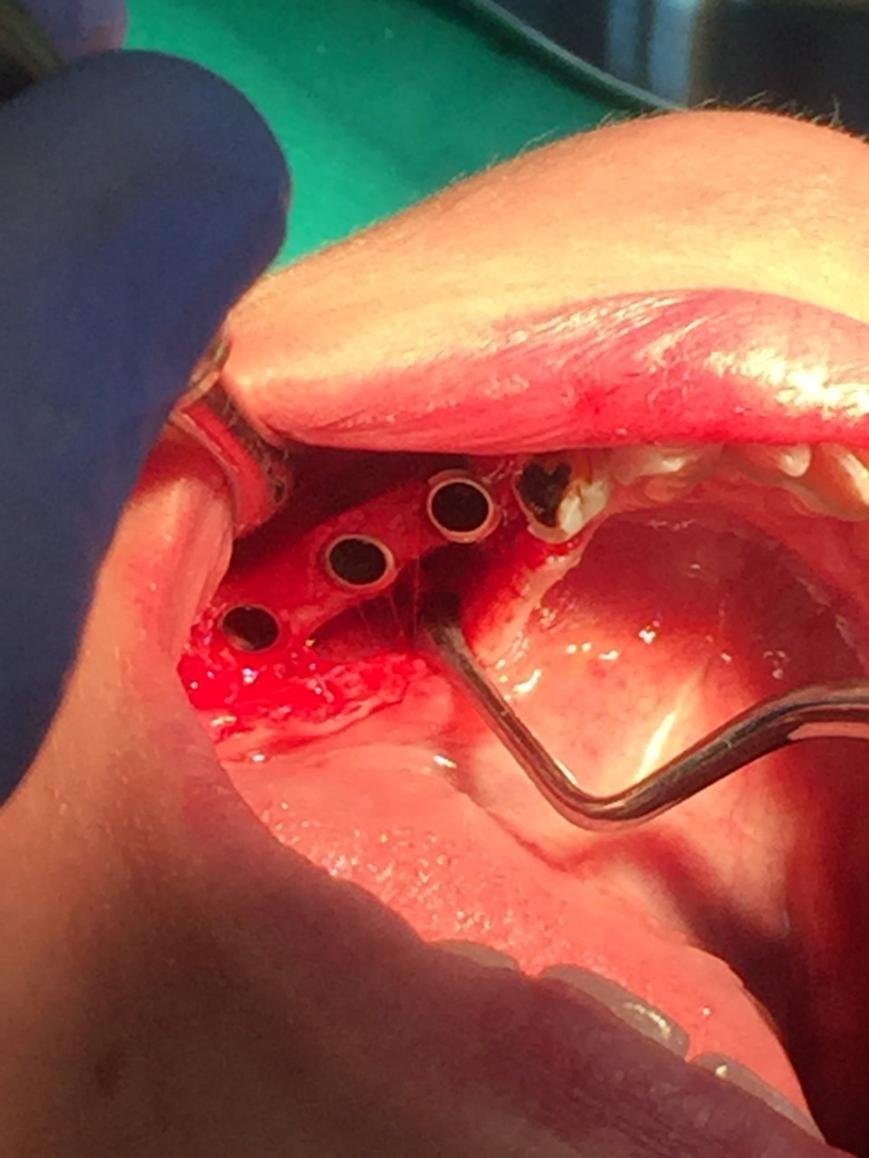

Іноді після тривалої відсутності зубів на одній ділянці або через носіння знімних протезів може спостерігатися деградування кістки верхньої щелепи і зменшення її в обсязі. У такому разі, перш ніж виконувати імплантацію, знадобиться пересадка кістки, після якої вже буде достатньо кісткової тканини для закріплення штифта.